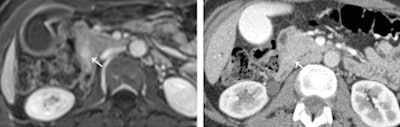

![]() |

| An ampullary carcinoma of 1.5 mm (arrow) is seen with contrast-enhanced T1-weighted MRI (left), but is not visible on contrast-enhanced CT (right). Image courtesy of Radiology. |